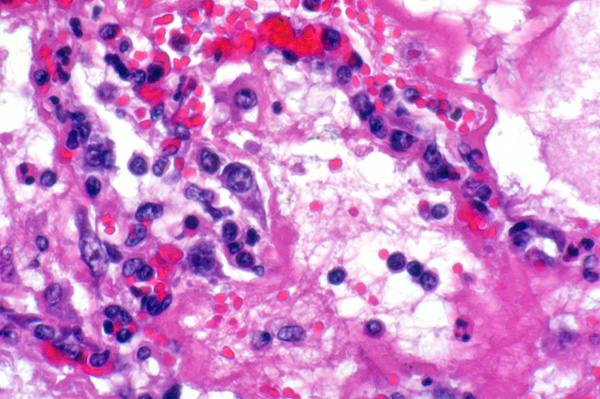

| 40x   |   Hematoxylin and Eosin | ||||

Occasional type II pneumocyte hyperplasia (arrowheads); lumina contain fibrin, edema, mild hemorrhage, and inflammatory cells.